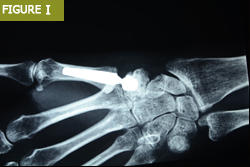

Bilek protezi, el bileğindeki hasarlı eklem yüzeylerinin değiştirilmesi için kullanılır. Bu işlem, bilek değiştirme ameliyatı olarak da bilinir ve genellikle artrit veya travma sonrası eklem hasarı olan hastalara uygulanır.

Her iki protez türü de titanyum veya seramik gibi dayanıklı malzemelerden üretilir ve uzun ömürlü bir çözüm sunar. Ancak, bilek eklemi değiştirme işlemi, el bileğinin daha karmaşık yapısı nedeniyle daha hassas bir cerrahi teknik gerektirir.

Bilek artroplastisi, bilek eklemlerinde ciddi hasar olan hastalar için uygulanan bir cerrahi yöntemdir. Bu işlem, özellikle bilek değiştirme ameliyatı olarak da bilinir ve hastaların ağrılarını azaltırken aynı zamanda eklem hareketliliğini de artırır.

Bilek artroplastisi, titanyum veya seramik gibi dayanıklı malzemelerden üretilen protezler kullanılarak gerçekleştirilir.

Bu işlem, özellikle artrit veya travma sonrası eklem hasarı olan hastalarda büyük bir rahatlama sağlar.

Ancak, her cerrahi işlemde olduğu gibi bilek artroplastisi de bazı riskler taşır. Enfeksiyon, protezde gevşeme veya eklem hareketliliğinde kısıtlılık gibi komplikasyonlar görülebilir. Bu nedenle, cerrahi öncesi detaylı bir değerlendirme yapılması ve hastanın risk faktörlerinin belirlenmesi gerekir.

El bileği artroplastisinde çeşitli implant modülleri de kullanılmıştır: